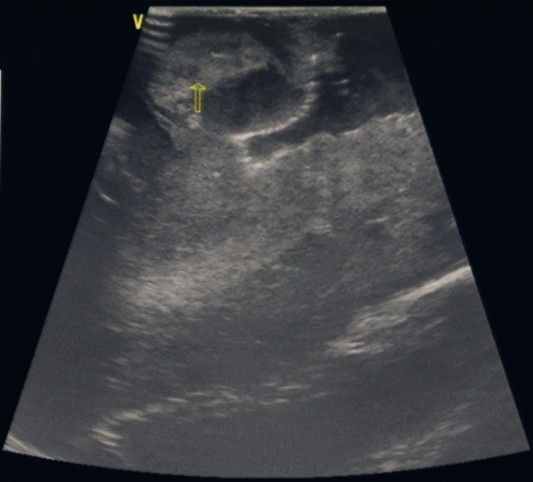

當(dāng)天,在B超室的大力支持和配合下,手術(shù)順利地進(jìn)行。術(shù)中應(yīng)用我院平常的床邊B超機(jī),選擇一個與術(shù)區(qū)相當(dāng)?shù)?span>B超探頭,裹上無菌膜即可使用。在切除腫瘤過程中,用B超探頭貼近術(shù)區(qū)探測腫瘤的范圍及位置,在B超引導(dǎo)下一步步切除腫瘤。當(dāng)手術(shù)行將結(jié)束時,再次應(yīng)用B超探測,清楚地發(fā)現(xiàn)腫瘤殘留,并進(jìn)一步切除干凈。結(jié)果,本例手術(shù)切除了95%以上的腫瘤組織,取得了圓滿的成功。

1. 腦腫瘤術(shù)中B超應(yīng)用

2.術(shù)中B超探測腫瘤

3.完全切除腫瘤